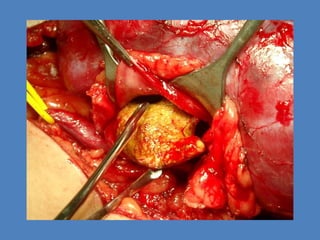

Cistolitotomia